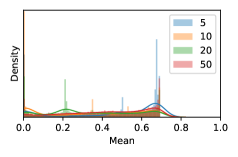

To model how different classifiers will respond to a given input , we assume that the prediction from classifier is sampled from a beta distribution that is characterized by two parameters by and . We further assume that is fixed to the same constant value for all ’s. Under this assumption, each input can be described by ( can be calculated since is fixed), easing further analysis. The Severity Level (SL) of the case represented by image can be characterized by the parameter . The larger the value of , the more severe the case of is. When and are close, the case is ambiguous as the distribution shifts towards being symmetric (i.e. signifying much disagreement among classifiers) rather than being one-sided (i.e. consensus among classifiers that is negative or positive). We provide a set of examples in Figure 2 and also Figure S.8 in the supplementary materials showing how the beta distribution can be used to capture diverse predictions given by an ensemble learner.

We conducted a case study on diagnosing diabetic retinopathy with ensembles of DL models. For benchmarking the performance of our ensemble-based solutions under the scheme described in Sec.3.3, we used two popular collections of diabetic retinopathy image data, the Kaggle Diabetic Retinopathy dataset [22] (hereafter referred to as “Kaggle-DR”) and the Messidor-2 dataset [23], each respectively consisting of and high resolution images. Diabetic retinopathy is graded into five SLs, as displayed in Figure 2. Following the problem setup used in previous papers [24], we trained models to distinguish the referable (SL2-4) cases from the non-referable ones (SL0 & SL1) (see Section B.1 for more detailed descriptions). We also tested our trained ensemble models on two o.o.d. image datasets (ImageNet [25] and CIFAR-10 [26]) to examine their capabilities of identifying o.o.d. inputs (see Section B in the supplementary materials).

In contrast, the MC-dropout method showed the worst overall performance among the three, as it can be seen from the high ratios of SL0 examples among the uncertain negatives in Figure 4. The histograms in Figure 2 provides another perspective to look into the phenomenon, where a decent proportion of MC-dropout model’s predictions on SL0 inputs entailed low confidence (far from 0 or 1), which from another angle explained why MC-dropout was less specific in terms of lower FNP; many no-DR inputs (i.e. SL0) were erroneously assigned high uncertainty by MC-dropout models.

As discussed in Section 5.1 and Section 5.3 in the main paper, the mean metric and the stacking ensemble will have better performance in the precision (specificity) on the ambiguous data. Here, more detailed results are shown in Figures S.3 & S.6 and Table S.1. Figures S.3 & S.4 show the histograms of the uncertainty score for Kaggle-DR and Messidor-2 datasets that are the in-distribution (i.d.) dataset in our experiment and FigureS.5 & S.6 show the histograms for ImageNet and CIFAR-10 datasets, which is the o.o.d. datasets in our experiment. Each group of histograms contains results from the three evaluated ensemble methods (stacking ensemble, MC-dropout and TTA) and the three uncertainty metrics (mean, var and kl). Additional detailed results not displayed in Figure 4 can be found in Table S.1, which shows the proportion of the data of different SLs varies across different . For comparison, we also included in Table S.1 the results from single learners, and the proportions of data of different SLs (before any selection was made).